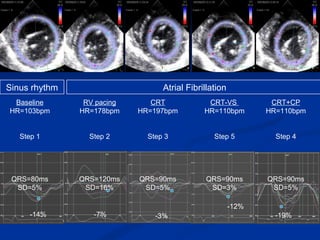

RV pacing HR=178bpm Step 2 QRS=120ms SD=16% CRT+CP HR=110bpm Step 4 QRS=90ms SD=5% CRT-VS  HR=110bpm Step 5 QRS=90ms SD=3% -12% -7% -14% Baseline HR=103bpm Step 1 QRS=80ms SD=5% Atrial Fibrillation Sinus rhythm Dog  #176 CRT HR=197bpm Step 3 QRS=90ms SD=5% -3% -19%

RV pacing HR=178bpmStep 2 QRS=120ms SD=16% CRT+CP HR=110bpm Step 4 QRS=90ms SD=5% CRT-VS HR=110bpm Step 5 QRS=90ms SD=3% -12% -7% -14% Baseline HR=103bpm Step 1 QRS=80ms SD=5% Atrial Fibrillation Sinus rhythm Dog #176 CRT HR=197bpm Step 3 QRS=90ms SD=5% -3% -19%